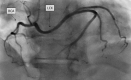

Case summary: We describe a 34-year-old man with a history of a single episode of chest pain. An ectopic origin on the part of the left circumflex (LCX) coronary artery from the proximal right coronary artery (RCA) was evident upon coronary computed tomography angiography. A positron emission tomography perfusion study revealed a stress-induced perfusion defect in the anomalous LCX territory (infero-posterior wall). The patient experienced dyspnoea and ST-segment depression in electrocardiography, suggestive of myocardial ischaemia during the maximal bicycle ergometer stress test. No mechanical compression or stenosis was seen upon invasive coronary angiography. The left ventricular perfusion normalized after the initiation of beta-blocker medication.